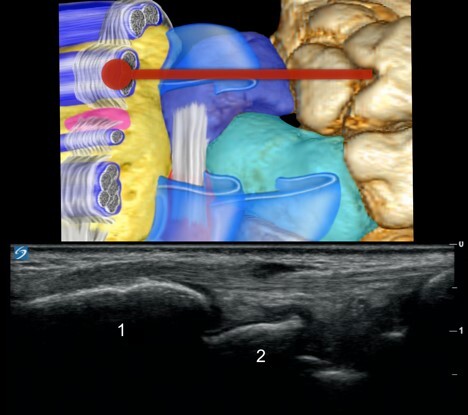

Dorsal Wrist Synovitis Longitudinal - Lateral Graphic and Image

Radius

Scaphoid